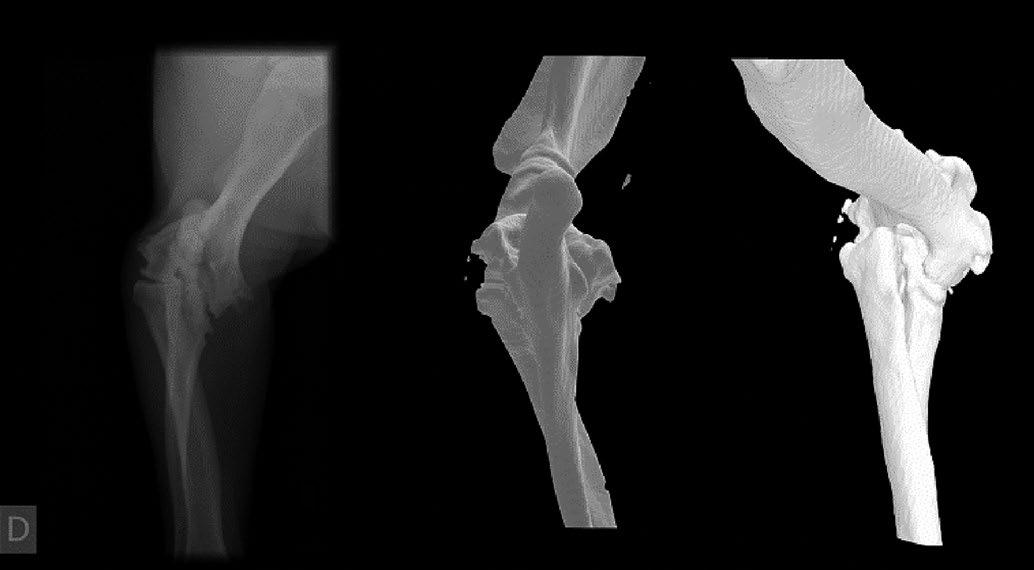

Issuu converts static files into: digital portfolios, online yearbooks, online catalogs, digital photo albums and more. Sign up and create your flipbook.